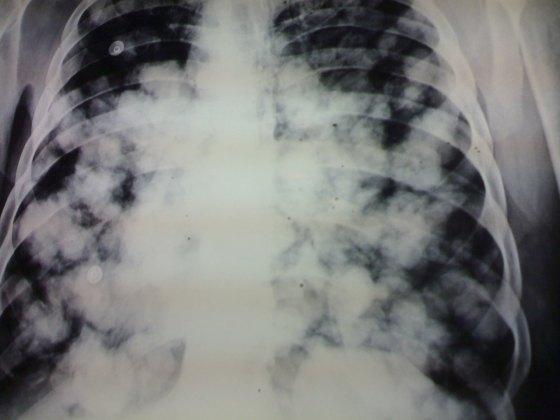

Fluffy-cotton appearance pneumonia